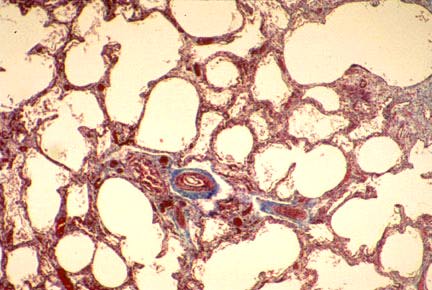

Post-surfactant BPD with less fibrosis and arrest in lung development resulting in fewer though larger alveoli.